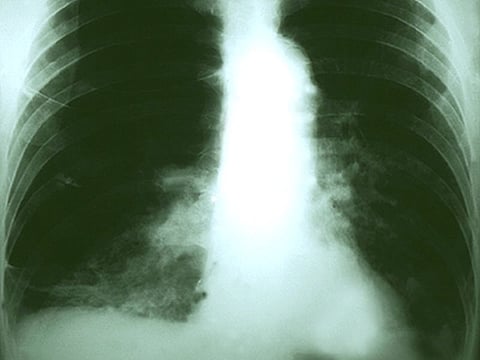

DOMINGO, 3 de junio de 2018 (HealthDay News) -- Un medicamento para el cáncer que potencia al sistema inmunitario supera a la quimioterapia para combatir al cáncer de pulmón avanzado, muestra un nuevo ensayo.

Para ver qué tan efectivo puede ser el pembrolizumab en general, Lopes y sus colaboradores asignaron al azar a 1,274 pacientes con un cáncer de pulmón avanzado a recibir pembrolizumab o quimioterapia. El periodo promedio de seguimiento fue de casi 13 meses.

Los investigadores encontraron que todo el que recibió pembrolizumab tuvo una supervivencia promedio más larga que los que se sometieron a quimioterapia: unos 16.7 frente a 12 meses.